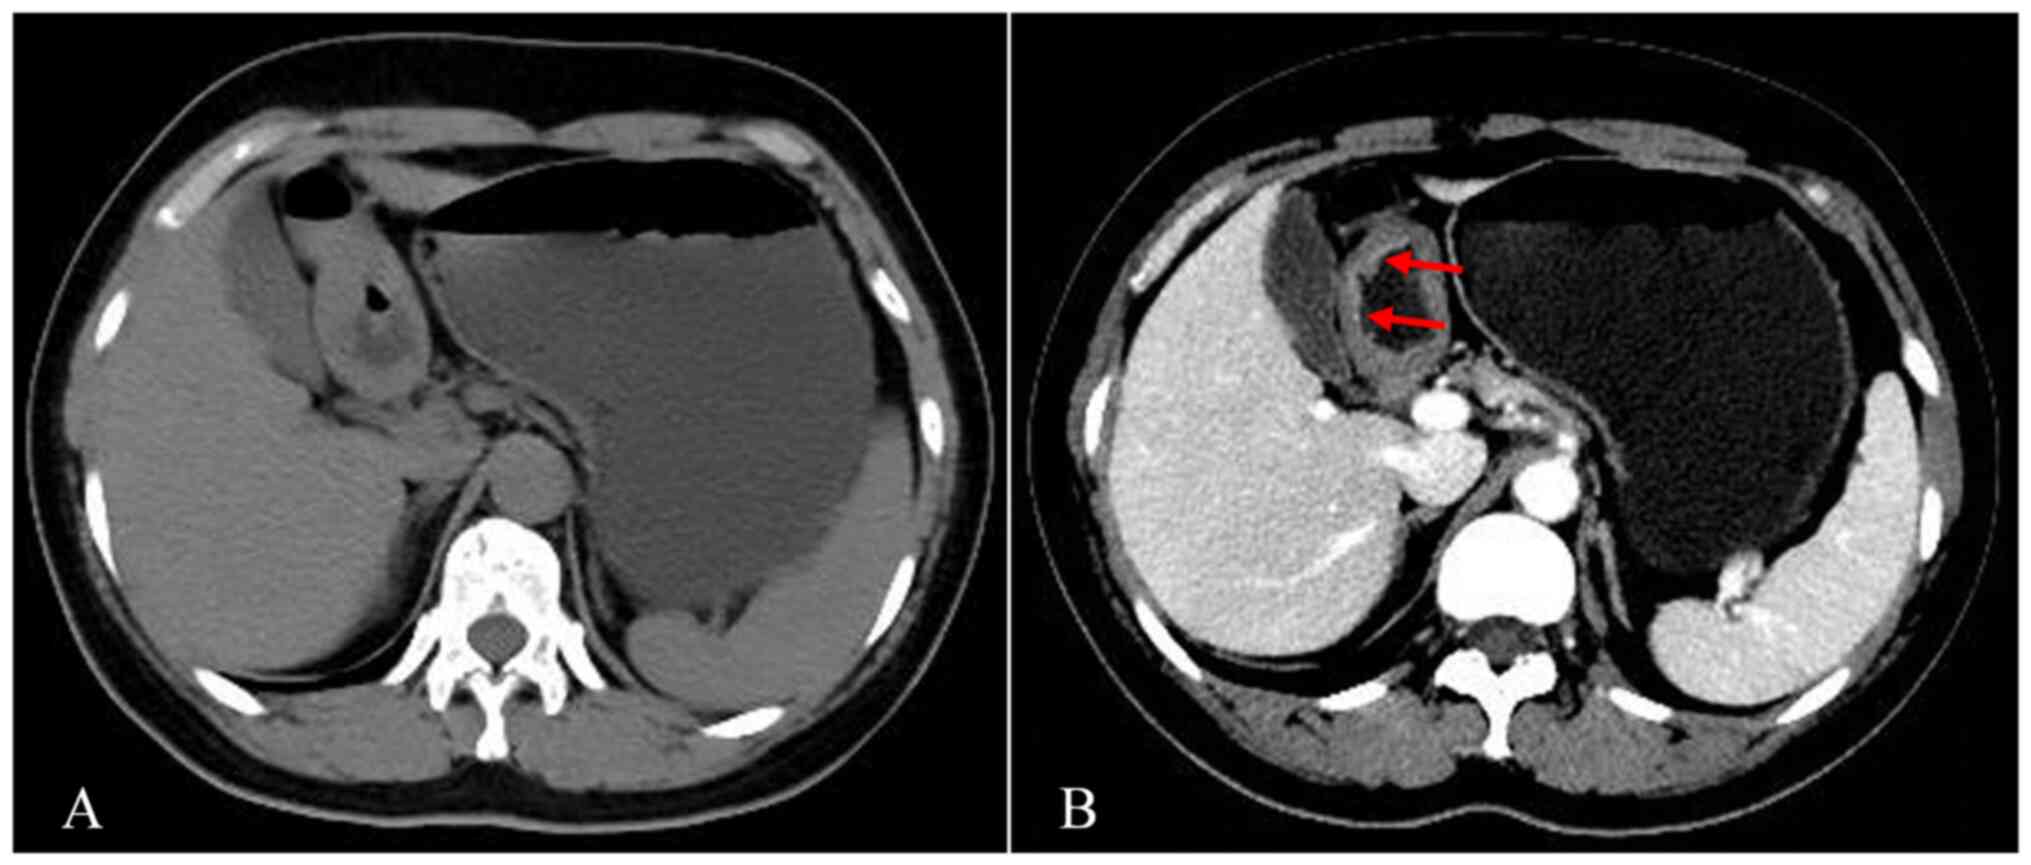

The ‘double‑track sign’: A novel CT finding suggestive of the diagnosis of T1a gastric cancer

Effective identification of T1a stage cancer is crucial for planning endoscopic resection for early gastric cancers. The present study aimed to determine the diagnostic value of the double‑track sign in patients with T1a gastric cancer using computed tomography (CT) imaging. A total of 152 patients diagnosed with pathologically proven T1a gastric cancer at The First Affiliated Hospital of Zhengzhou University (Zhengzhou, China) between July 2011 and August 2021 were retrospectively reviewed. The control group consisted of 2,926 patients with gastritis. Clinical data, including patient characteristics and preoperative CT imaging findings with gastric morphological features, were reviewed and analyzed. Out of 51 patients with T1a gastric cancer finally included, 31 (60.8%) exhibited local double‑track enhancement changes of the stomach, referred to as the ‘double‑track sign’, on CT images. In addition, four patients (7.8%) had well‑enhanced mucosal thickening of the gastric wall. Of the 2,926 control subjects, none had any double‑track sign and six patients (0.2%) had local gastric wall thickening with abnormally strengthened enhancement. In conclusion, a double‑track sign on CT images is beneficial in the diagnostic differentiation of T1a gastric cancer.